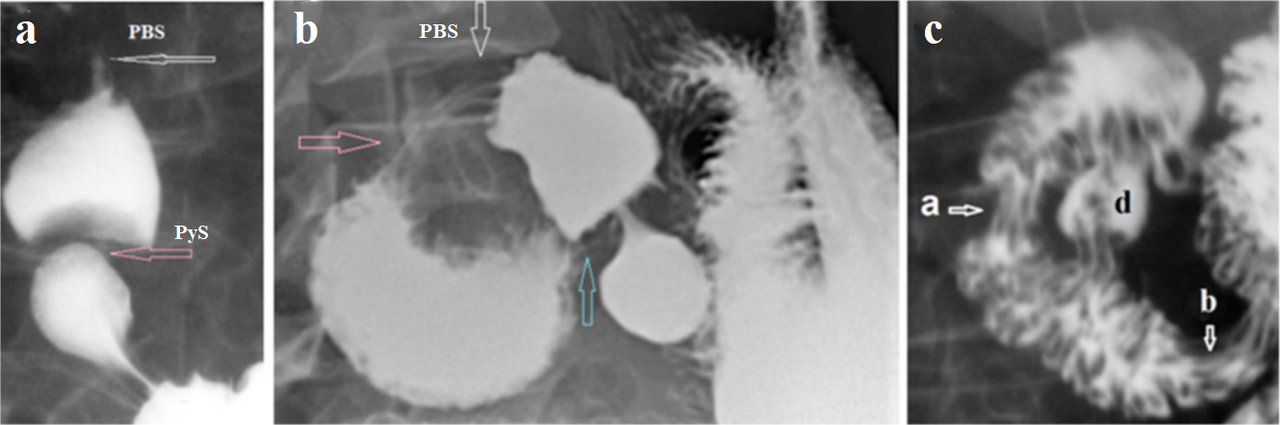

In recent decades, a completely different picture has been described as normal SO anatomy. During cholangiography, in the area between the CBD and the papilla, two areas of contraction are identified, between which there is a wide cavity called the ampulla. When the peristaltic wave reaches SO, “first the upper part, the sphincter choledochus, opens from above downwards, the contrast enters the ampulla. Then the sphincter choledochus contacts, again from above downwards, isolating a small portion of contrast in the ampulla. The distal sphincter opens, and the systolic volume falls into the duodenum” [10]. These authors, examining serious patients who required cholangiography, have no reason to consider the obtained results as anatomically normal. It is sufficient to compare the radiographs in Figure 1bc with the radiograph in Figure 2a to see that the ampulla is combined with a sharp dilation of the common duct. The ampullae appears in all sphincter zones, if sphincters function impaired. Normally, the last peristaltic wave creates threshold pressure for sphincter opening. The ampulla represents the last peristaltic wave in a wide bore channel, which reduces its ability to create threshold pressure for SO opening. To create a threshold pressure, a functional sphincter arises, and it contraction allows the ampulla to create a higher pressure and inject a bolus into the lumen with a higher pressure than in the CBD (Figure 2. a, b) [11].

Figure 2. (a) Cholangiography for severe SO damage, and (b) a diagram for it. (d – duodenum; CBD – common bile duct; a – ampulla located between the shortened SO - blue arrow, and the functional sphincter - red arrow). (c) Vesicoureteral reflux. The ampulla is located between the vesicoureteral sphincter - blue arrow, and the functional sphincter - red arrow. (d) Gastroesophageal reflux. The phrenic ampulla is located between the LES and the functional (proximal) sphincter (PS). (e). A patient with enteritis. The ampulla is located between the ileocecal valve - blue arrow, and the functional sphincter - red arrow.

It follows that the presence of an ampulla is evidence of severe SO damage.